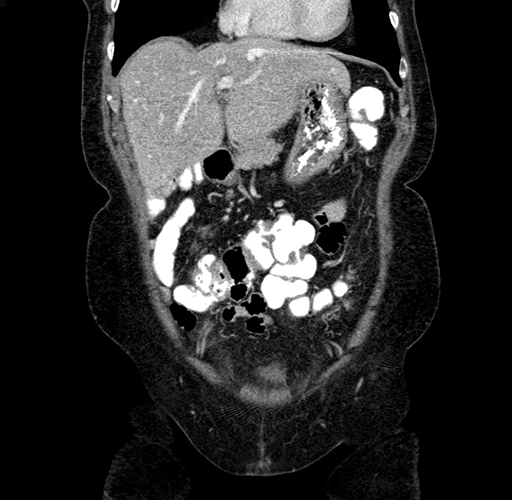

Pre-Chemo: Coronal Venous

Coronal Venous